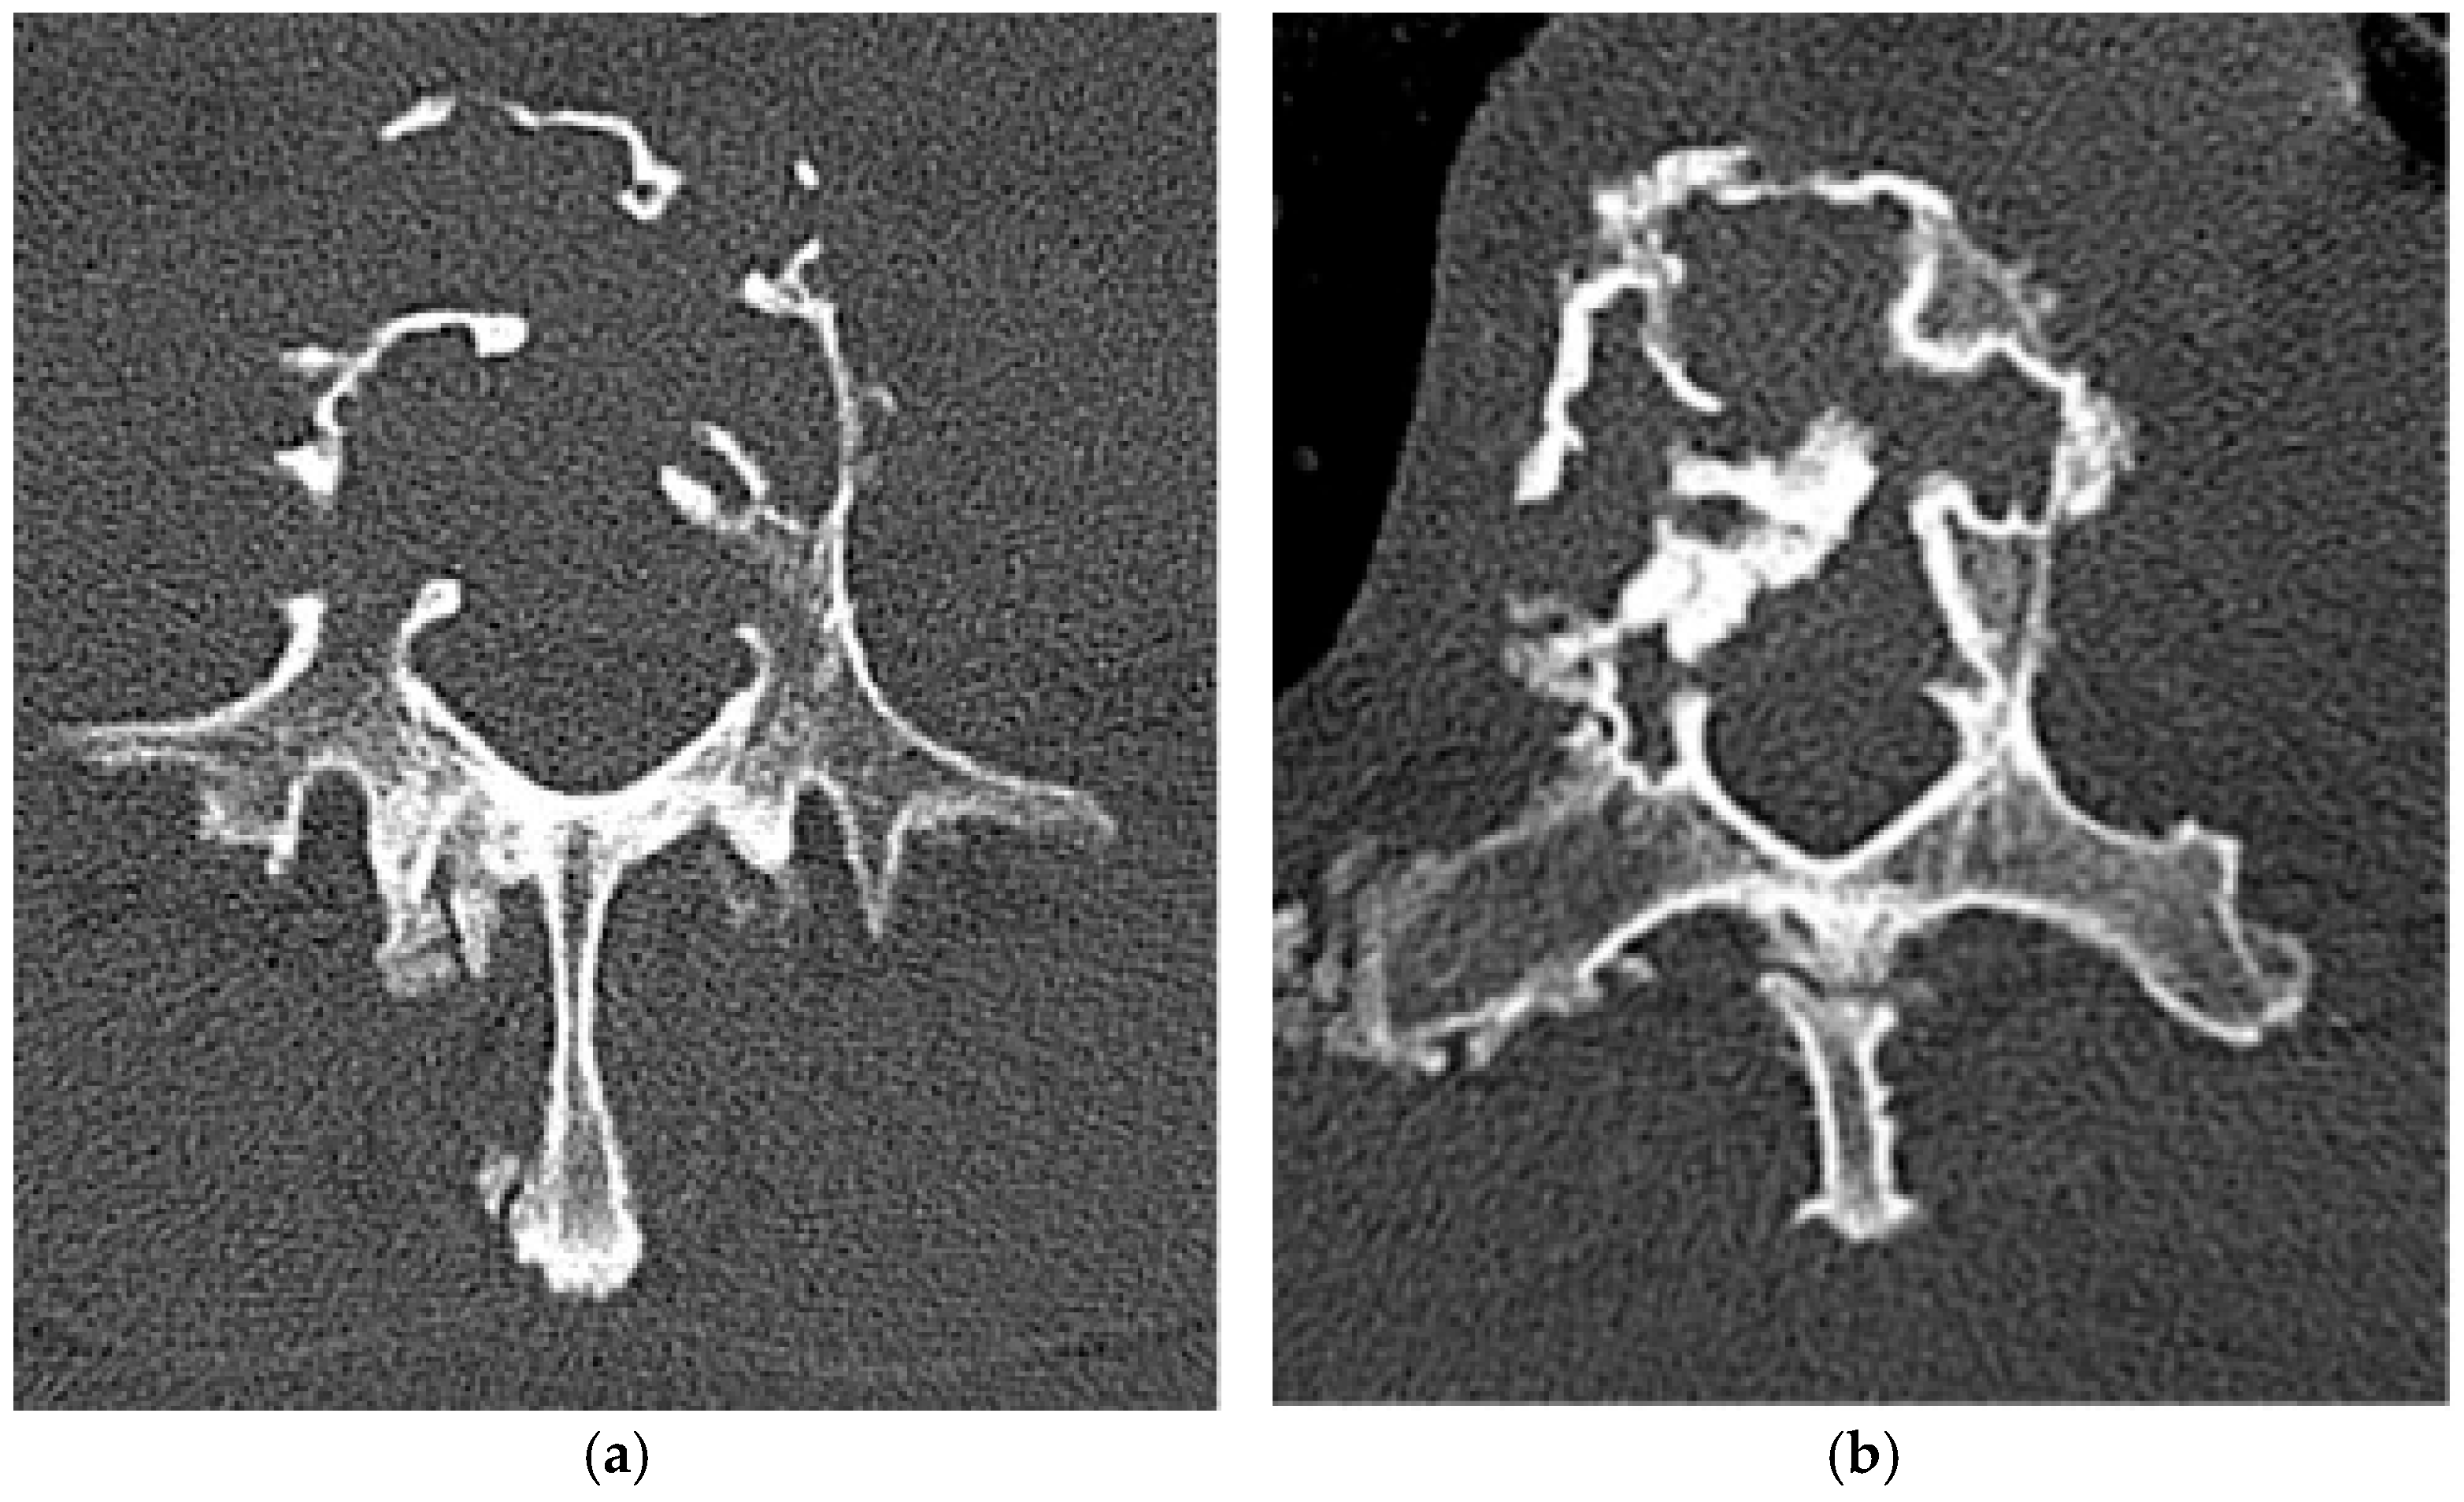

2.2.1. Osteochondroma

2.2.2. Chondroblastoma